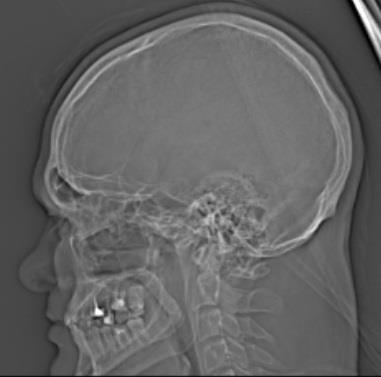

Был на днях на приёме у врача невролога. Вот он мне и сказал, что я здоров: по записям в результатах компьютерной томографии моё здоровье в пределах нормы.

А платный невролог в диагнозе бред написал (был у него прошлой осенью и тогда КТ головного мозга делал).

Ещё я теперь знаю, как на фото мой череп выглядит.